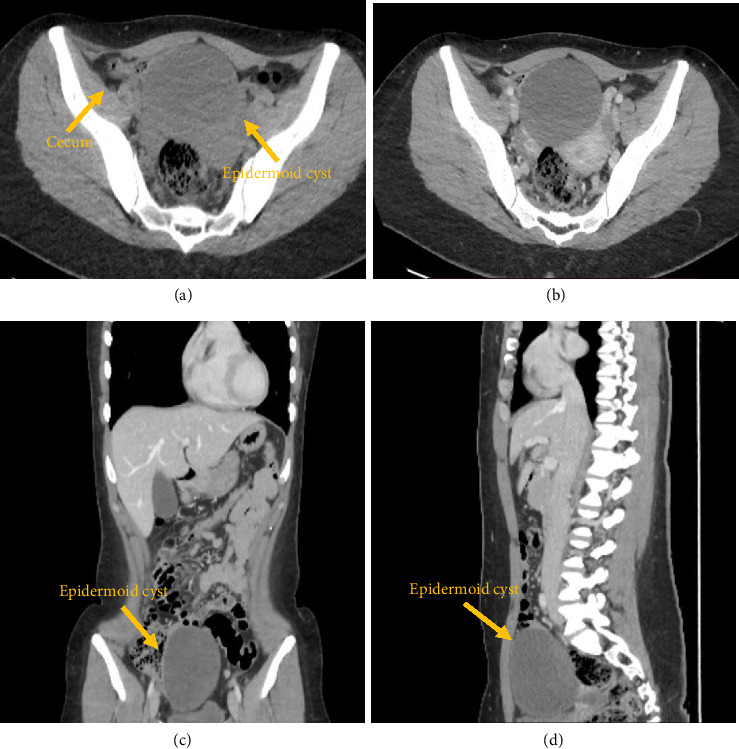

盲肠表皮样囊肿(CEC)是一种罕见的良性病变;起源可为获得性或先天性,但发病机制尚不清楚。我们提出一个病例报告,病人与盲肠囊肿治疗半结肠切除术。组织病理学显示盲肠表皮样囊肿(EC)。病例介绍:一名28岁女性因腹痛入院,无明显既往病史。行CT和MRI扫描,发现盆腔前部有一个大的囊性肿块。成像技术能够定位肿瘤的位置和大小;然而,他们并没有提供一个结论性的诊断。鉴别诊断为阑尾黏液囊肿、重复囊肿或子宫内膜异位囊肿形成。行腹腔镜右半结肠切除术;肿块未与周围脏器粘连。宏观表现为104 × 83 × 68 mm盲肠壁上的不规则腔外囊性病变。镜下,囊壁内衬角化层状鳞状上皮。未发现恶性肿瘤。因此,组织病理学评估导致最终诊断EC。结论:ECs是一种罕见的良性肿瘤,可以是后天的,也可以是先天性的。它们在临床和影像学表现上各不相同;病变可伴有非特异性症状或无症状。在性别分布和年龄上都有很大的异质性。影像技术是有用的,但最终的诊断只能在肿瘤完全手术切除和组织病理学检查后才能做出。

Introduction: Cecal epidermoid cyst (CEC) is a rare and benign lesion; the origin can be acquired or congenital, but the pathogenesis remains unclear. We present a case report of a patient with a cecal cyst treated by hemicolectomy. Histopathology revealed an epidermoid cyst (EC) of the cecum. Case Presentation: A 28-year-old woman was admitted to the hospital with abdominal pain, without significant past medical history. CT and MRI scans were performed, and a large cystic mass in the anterior portion of the pelvic region was detected. Imaging techniques managed to localize the site and dimensions of the neoplasm; however, they did not provide a conclusive diagnosis. The differential diagnosis was made with appendiceal mucocele, duplication cyst, or endometriotic cyst formation. Laparoscopic right hemicolectomy was performed; the mass did not present with any adhesions with the surrounding organs. Macroscopically, the mass appears as irregular extraluminal cystic lesion arising from the cecal wall of 104 × 83 × 68 mm. Microscopically, the cystic wall was lined by keratinized stratified squamous epithelium. No malignant findings were identified. Thus, the histopathologic evaluation leads to the final diagnosis of EC. Conclusions: ECs are rare benign neoplasms that can be acquired or congenital. They can vary both in their clinical and imaging presentation; the lesion can be associated with nonspecific symptoms or be asymptomatic. A wide heterogeneity both in sex distribution and age is observed. Imaging techniques are useful, but the final diagnosis can be made only after the complete surgical excision of the neoplasm and its histopathological examination.